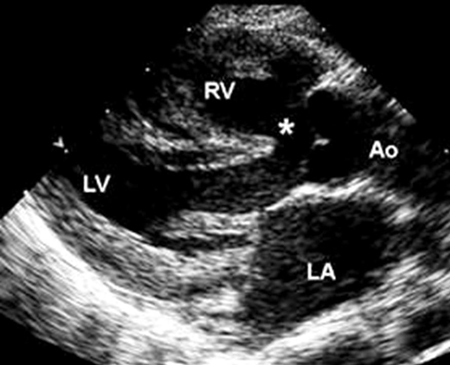

Imagen de ecocardiografía de eje largo paraesternal en un paciente con tetralogía de Fallot. Hay cabalgamiento de la aorta sobre la comunicación interventricular (*). (AI) aurícula izquierda; (VD) ventrículo derecho; (VI) ventrículo izquierdo